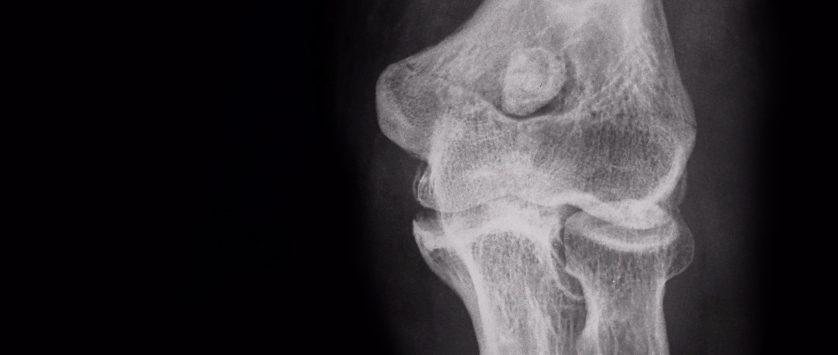

Pseudoguzy hemofilowe